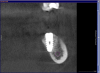

Phony_slob Опубликовано 30 июня, 2013 Поделиться Опубликовано 30 июня, 2013 Что посоветуете делать? Точить седьмой или попробовать выпрямить ортодонтически? Если второй вариант, сколько это может занять времени? Ссылка на комментарий

red_butler Опубликовано 30 июня, 2013 Поделиться Опубликовано 30 июня, 2013 Этот снимок имеет геометрические искажения, поставте формирователь. Если позиция делает протезирование невозможным или заведомо провальным, я бы подключил ортодонта, причем толкать можно от Импланта 4 Ссылка на комментарий

Luger Опубликовано 3 июля, 2013 Поделиться Опубликовано 3 июля, 2013 Что посоветуете делать? Точить седьмой или попробовать выпрямить ортодонтически? Если второй вариант, сколько это может занять времени?ТМА Абатмент и винтовая фиксация..как более быстрое решение вопроса. Ссылка на комментарий

Plombir Опубликовано 16 июля, 2013 Поделиться Опубликовано 16 июля, 2013 Не изменив ориентацию 4.7, не избежать кармана со всеми вытекающими 1 Ссылка на комментарий